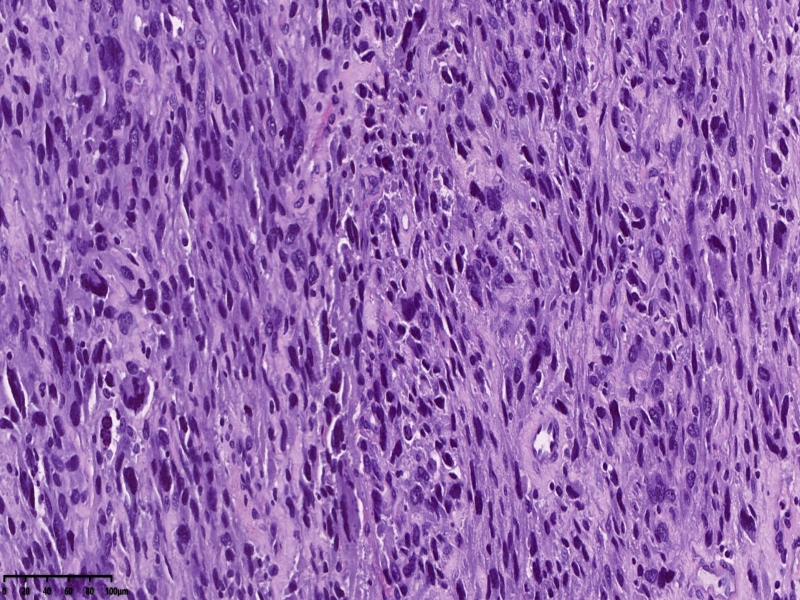

镜下可见肌间可见梭形瘤细胞,细胞核畸形,多核瘤巨细胞。坏死。

会诊结果:子宫体间叶组织来源的肿瘤,形态学符合恶性。依据免疫组化结果,可排除肌源性肿瘤、胃肠间质瘤、子宫内膜间质肿 瘤、神经源性肿瘤、孤立性纤维性肿瘤等。 考虑可能为纤维肉瘤。